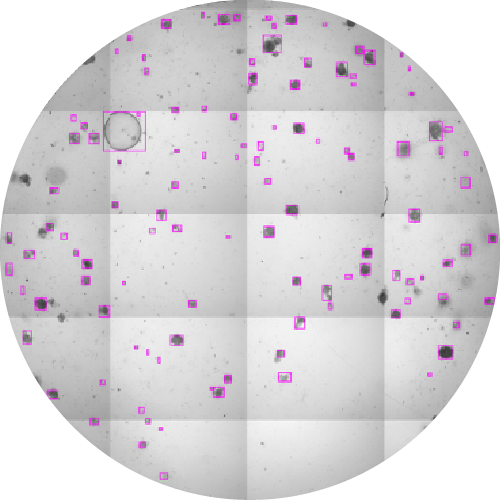

UQOB – Uncertainty Quantification in Object-detection Benchmark

Helmholtz Centers: Helmholtz Munich (HM), German Cancer Research Center (DKFZ)

Project lead: Dr. Marie Piraud, HM, Head of the consultant team, Helmholtz AI

Data: High-resolution 2D microscopy images of organoids from human and murine lung and colon tissues, annotated with bounding boxes and class labels

Challenge: Creating a benchmark dataset for object-detection and Uncertainty Quantification (UQ) in a multi-rater setting, to address annotation variability and AI model evaluation.